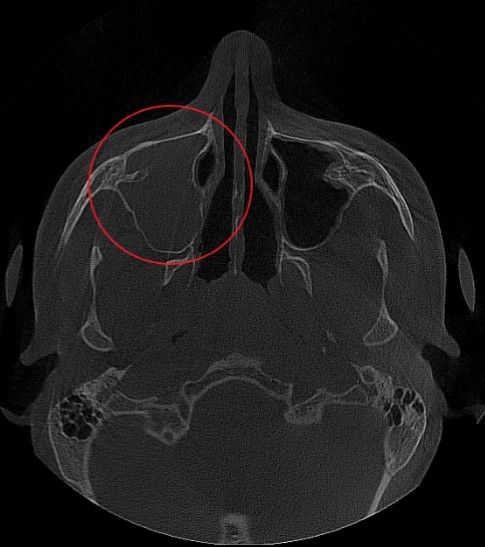

Проведена компьютерная томография околоносовых пазух, которая подтвердила наличие правостороннего гемисинусита (воспаление нескольких пазух с одной стороны), как следствие периодонтита зуба 1.6.

Представлено КЛКТ околоносовых пазух до начала лечения. Выделена зона воспаления пазух.